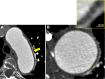

CLINICAL INTRODUCTION: A retired 59-year-old woman presented to the cardiology clinic concerned with cardiac pulsations that were visible on her chest wall. These were not associated with dyspnoea, syncope or chest discomfort.Of note, 8 years previously, she complained of recurrent nocturnal diaphoresis and 5 kg weight loss. Blood sampling at that time revealed a microcytic anaemia, reactive thrombocytosis and raised inflammatory markers (erythrocyte sedimentation rate 99 mm/hour, C-reactive protein 161 mg/L). Following an episode of transient diplopia, ophthalmoscopy demonstrated a cotton wool spot in the left inferotemporal retinal arcade. She commenced a 2-year tapering course of 1 mg/kg prednisolone.On examination, she had a lean physique with a supine blood pressure of 162/60 mm Hg and palpable Corrigan's pulse. She had a prominent apical pulsation and a loud early diastolic murmur was present at the left sternal edge radiating to the apex. Echocardiography showed severe central aortic regurgitation and a dilated aortic root (see online supplementary figure 1). Cardiac CT was performed to clarify the diagnosis (figure 1).DC1SP110.1136/heartjnl-2017-312193.supp1Supplementary file 1 heartjnl;104/3/273/F1F1F1Figure 1Contrast-enhanced CT of the thorax at index presentation (A) and 6 months (B). Prospective ECG-gated cardiac CT angiogram (75% R-R interval) performed at 8 years from index presentation (C) with a stretched multiplanar reconstruction of the aortic annulus, aortic root and thoracic aorta (D).